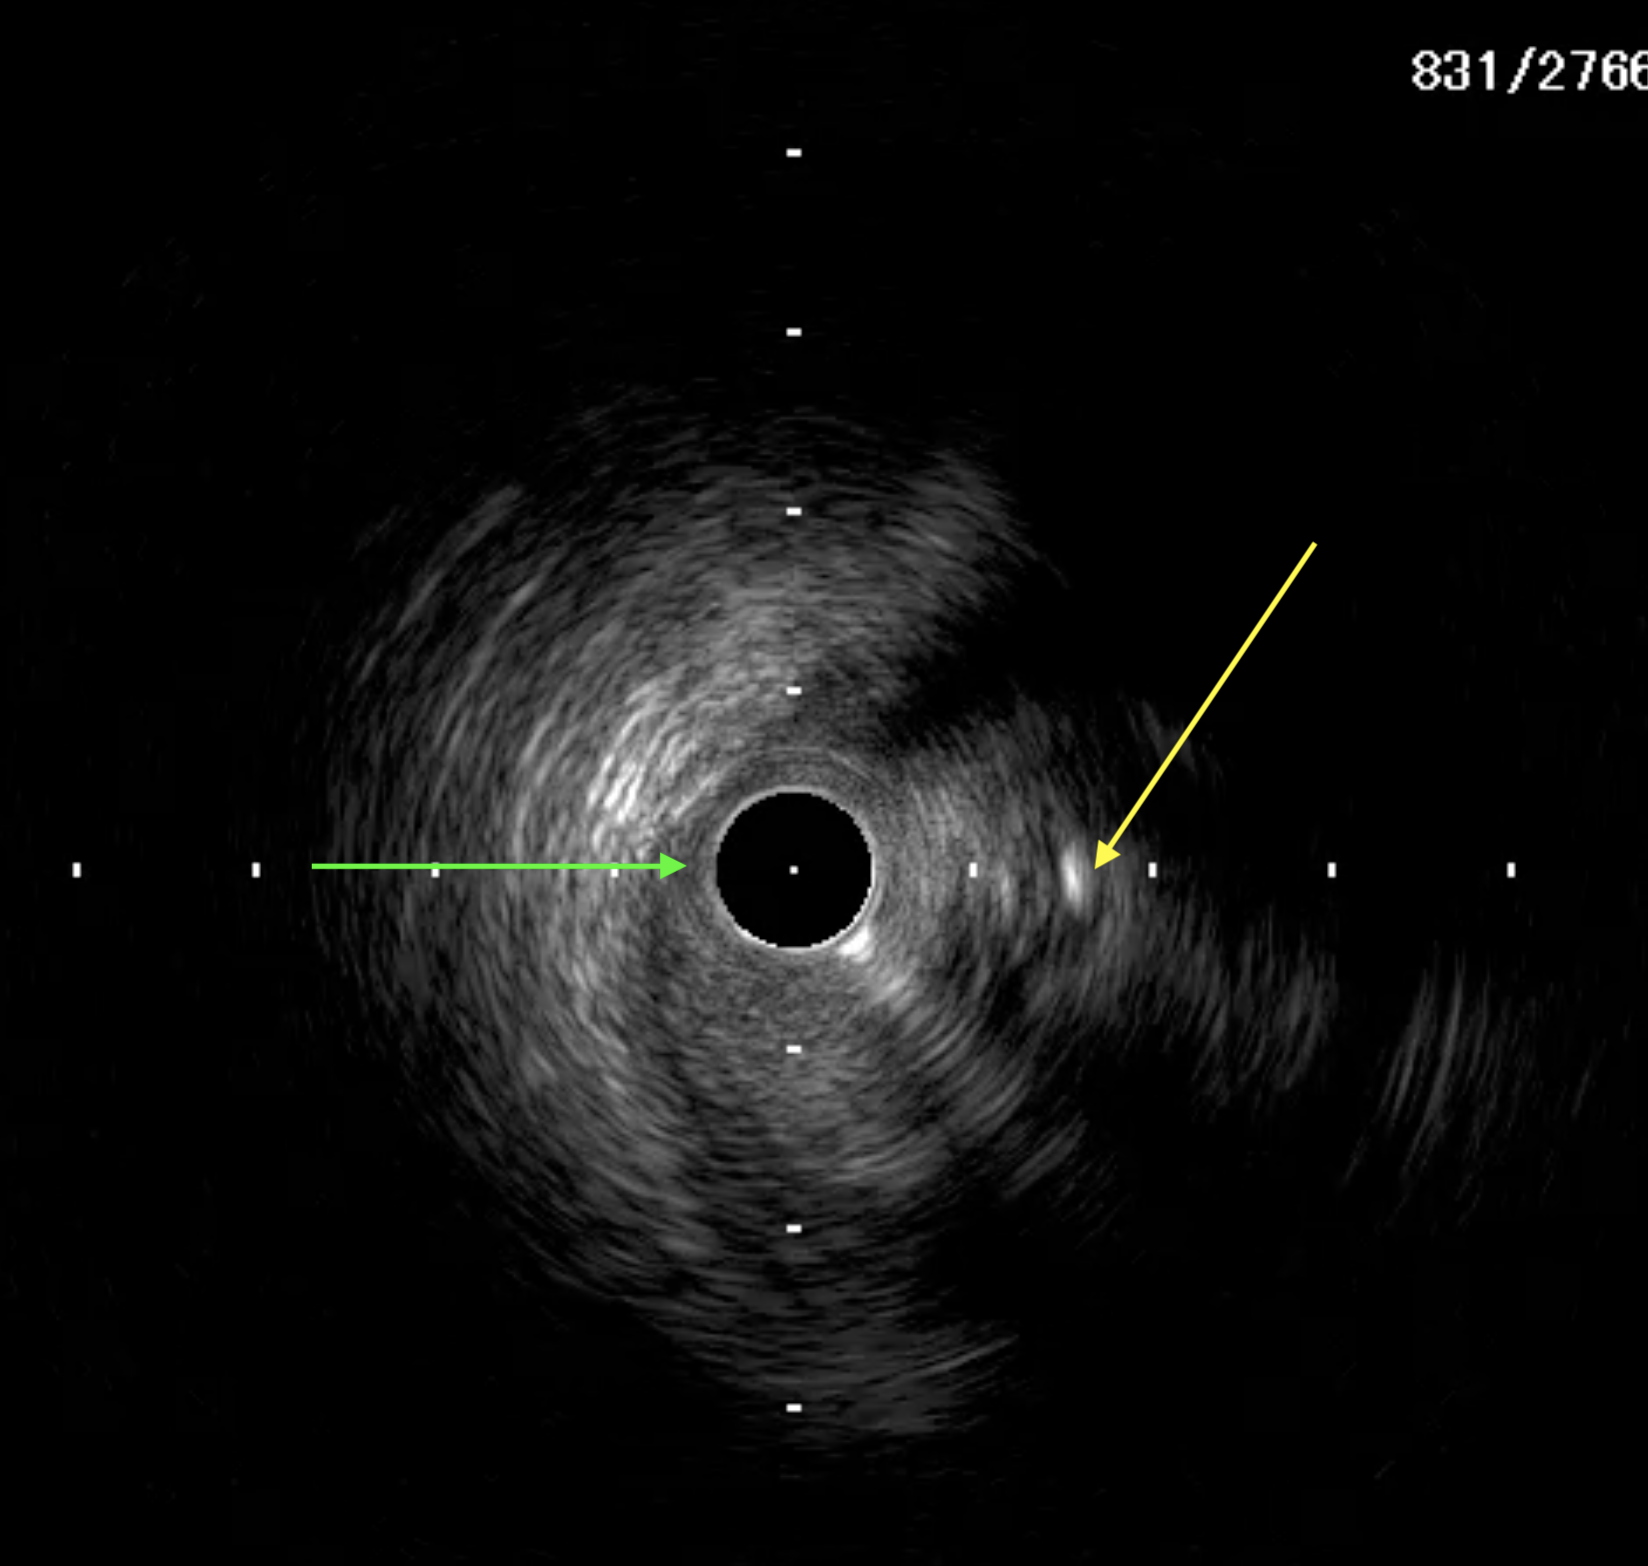

A 51-year-old man presented with stable angina and previously failed right coronary artery (RCA) CTO PCI. During RCA CTO PCI (Figure 1), the wire was inserted into the extraplaque space (Figure 2, Video 1). Intravascular ultrasound (IVUS) showed a hematoma (Figure 3A, Video 2). Live 3-dimensional tip detection IVUS wiring was successful (Figure 4, Video 3). A FineCross microcatheter (Terumo) was placed over the first wire into the extraplaque space and blood was withdrawn by connecting a negative indeflator to the microcatheter. Stents were deployed (Figure 5) and postdilated. Post-IVUS showed almost complete resolution of the hematoma (Figure 3B, C; Video 4) with good results (Figure 6, Video 5).